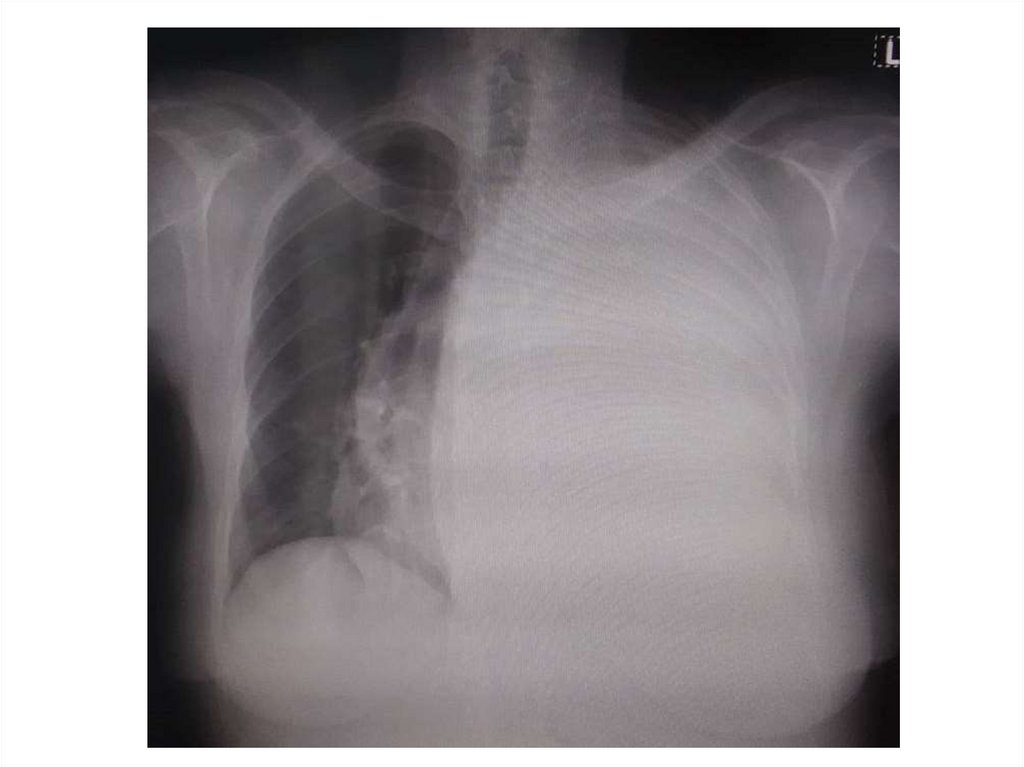

На рентгенограмме грудного отдела

позвоночника в прямой проекции стоя

определяется отклонение оси

позвоночника вправо с

формированием сколиотической дуги

на уровне Th6-Th11, угол сколиоза 1100

(4 степень сколиоза)